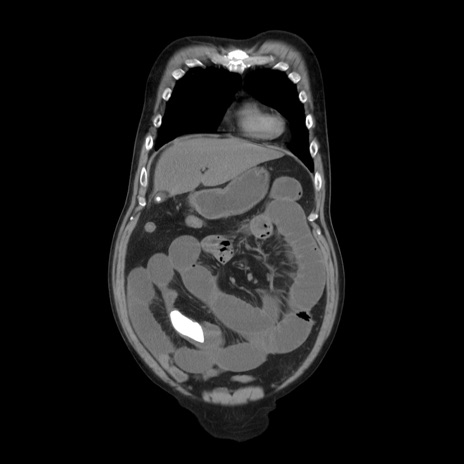

症例20(冠状断像)

【症例】 60歳代男性

【主訴】 腹部膨満、嘔吐

【現病歴】5日前頃より倦怠感を認め食事量減少し4日前の朝嘔吐、食事摂取困難となった。 3日前近医受診し点滴施行され整腸剤などを処方された。 当日他院を受診し、腹部膨満著明、炎症反応の上昇(CRP10.8、WBC11200)あり、紹介受診となる。

【身体所見】 意識JCS1 受け答えがはっきりしないBP 111/57mHg、 P 67bpm、、BT35.2°C、SpO2 97%(RA)、 腹部:膨隆、打診で鼓音あり、全体的に圧痛有り、腸蠕動音(-)、反跳痛ははっきりせず。

【データ】WBC 11400、CRP 14.20

横断像